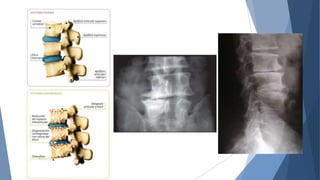

 enfermedad esquelética sistémica,caracterizada

por baja masa ósea y deterioro en la

microarquitectura del tejido óseo, que origina

fragilidad ósea aumentada con el consecuente

aumento en el riesgo de fractura“

 La osteoporosis es la causa más común de

fracturas, afectando al 20% de las mujeres

postmenopáusicas en EE.UU y se estima una

población de 7.8 millones a nivel mundial y que

el año 2040 el problema se habrá triplicado.

 El riesgo de por vida de sufrir una fractura a

partir de los 50 años es de 40% para las mujeres

y de un 13% para los hombres, debido a la

osteoporosis.